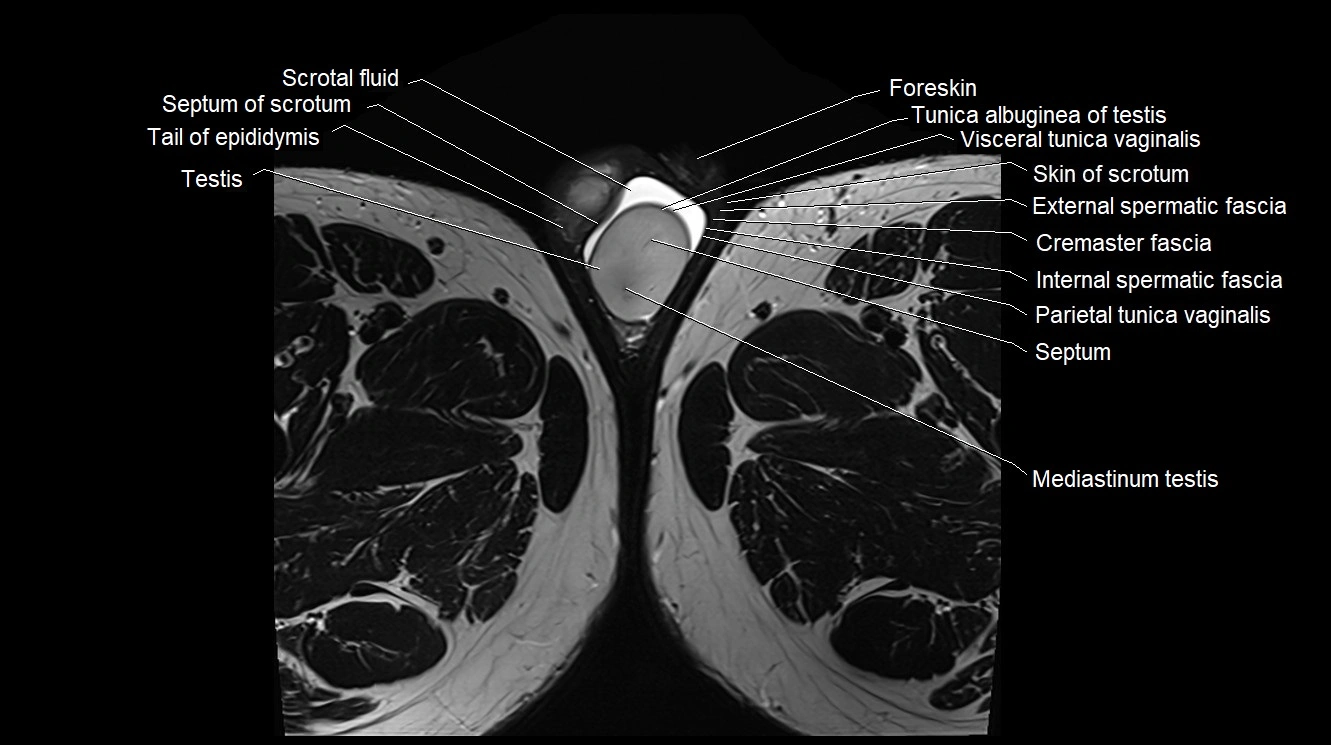

- Cremaster fascia

- External spermatic fascia

- Foreskin

- Internal spermatic fascia

- Lobule of testis

- Mediastinum testis

- Parietal tunica vaginalis

- Scrotal fluid

- Septum of scrotum

- Skin of scrotum

- Tail of epididymis

- Testis

- Tunica albuginea of testis

- Visceral tunica vaginalis